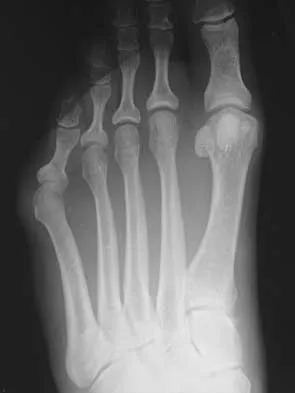

Question 3

A 19-year-old woman has had a painful prominence on the lateral border of her fifth metatarsal head since she was a young girl. Nonsurgical management, including the use of a wide toe box shoe, has failed to provide relief. Examination reveals a callus over the lateral prominence and on the plantar portion as well. A clinical photograph and a radiograph are shown in Figures 34a and 34b. Treatment should consist of

Explanation

The type of deformity described is a type 2 bunionette. There is often a congenital component to this deformity. The bowing of the fifth shaft differentiates a large intermetatarsal angle from a type 3 deformity. A distal chevron osteotomy corrects 1 degree in the intermetatarsal angle for every 1-mm shift. Because of limitations in the width of the fifth metatarsal neck, the allowable shift is generally 3 to 4 mm. This shift will not compensate for the large intermetatarsal angle. The floating osteotomy has a high rate of delayed union/nonunion and a low satisfaction rate. Metatarsal head excision has a high complication rate, including severe shortening, transfer metatarsalgia, stiffness, and pain. A more proximal procedure is necessary to correct the large intermetatarsal angle and the lateral bowing. The osteotomy of choice is a diaphyseal shaft osteotomy. Because this patient has a plantar callosity and a lateral callosity, the osteotomy is angled superiorly to elevate the fifth shaft with the shift, eliminating overload of the plantar metatarsal head and subsequent callus formation. Shereff MJ, Yang QM, Kummer FJ, Frey CC, Greenidge N: Vascular anatomy of the fifth metatarsal. Foot Ankle 1991;11:350-353. Coughlin MJ: Treatment of bunionette deformity with longitudinal diaphyseal osteotomy with distal soft tissue repair. Foot Ankle 1991;11:195-203.